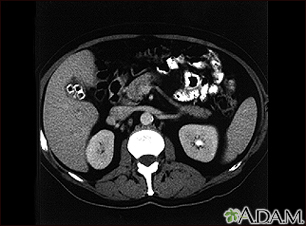

Colecistolitiasis. TC del abdomen superior mostrando múltiples cálculos biliares.